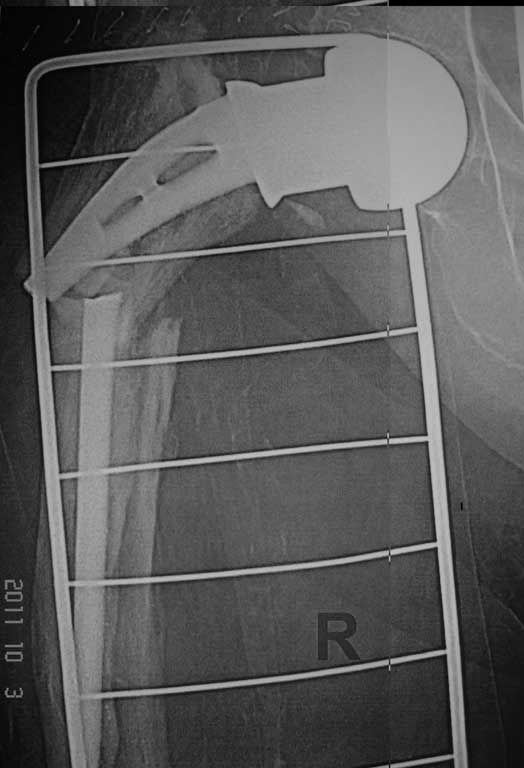

Добрый вечер. Уважаемые коллеги, впервые столкнулись

с перипротезным переломом правой бедренной кости.

Женщина 86 лет, оперирована нами 6 лет назад по поводу перелома шейки правой бедренной кости . Травма двое суток назад-падение в квартире.

Наши мысли по поводу данного случая - удаление протеза сломанной ножки и замена ревизионной цементной ножкой и модульной головкой , при этом не выполнять вскрытие кортикальной стенки в виде окна, для того чтобы убрать остатки цемента ,т.к эта процедура увеличит интраоперационную травму и кровопотерю, а с помощью рашпилей разработать канал, ввести в дистальный отломок цемент и посадить ножку,если будет нужно наложить серкляжные швы.